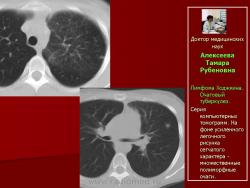

Рис. 6. Та же б-ная А. Лимфома Ходжкина. Очаговый туберкулез.

Серия компьютерных томограмм. На фоне усиленного легочного рисунка сетчатого характера - множественные полиморфные очаги.

Следует отметить, что не всегда при туберкулезе легких отмечалась классическая скиологическая картина. Трудности в постановке диагноза туберкулеза возникали при появлении множественных полостных образований в легких с тонкими стенками на фоне неизмененной легочной ткани. В отдельных полостях определялись шаровидные массы, что заставило расценить выявленные в легких изменения как проявления аспергиллеза (рис. 7).

Рис. 7. Б-ного Р. Лимфома Ходжкина. В легочной ткани - полостные образования с шаровидным уплотнением внутри.

Однако при микроскопическом исследовании мокроты больного Р., страдающего лимфомой Ходжкина, были обнаружены микобактерии туберкулеза. На фоне противотуберкулезной терапии отмечена положительная динамика, а в дальнейшем и полная регрессия изменений в легких.